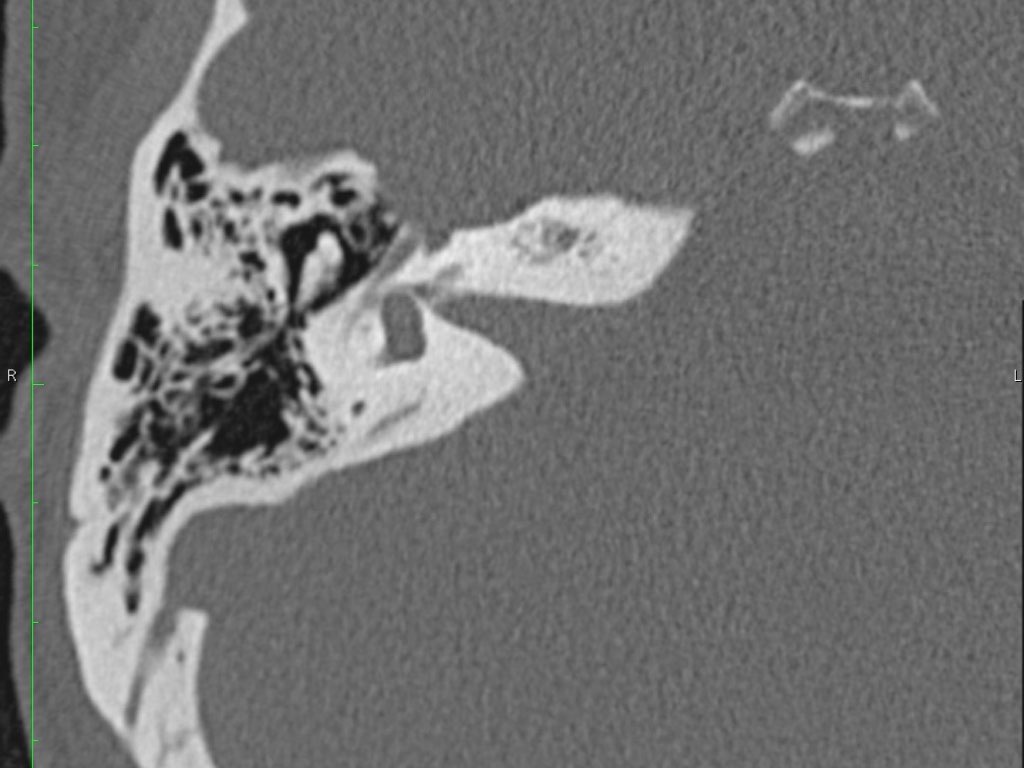

Trong bài tổng quan này, chúng tôi trình bày giải phẫu bình thường trên mặt phẳng cắt ngang (axial) và mặt phẳng cắt đứng ngang (coronal) của xương thái dương thông qua việc duyệt qua các hình ảnh.

Giải phẫu xương đá trên mặt phẳng cắt ngang (Axial)

Nhấp vào hình ảnh để phóng to.

Cuộn qua các hình ảnh.